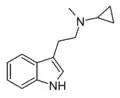

| McPT | artificial | H | CH3 | C3H5 | N-Methyl-N-cyclopropyltryptamine | 1373918-63-8 |